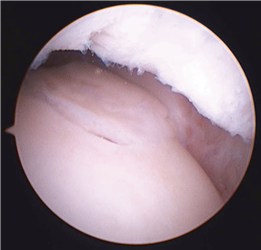

Conversely, hallux rigidus represents a degenerative cascade characterized by osteophyte formation, dorsal impingement, and progressive loss of sagittal plane motion at the first MTP joint. While trauma and inflammatory arthropathies can precipitate this condition, the most common etiology is idiopathic, often linked to an elevated or elongated first metatarsal (metatarsus primus elevatus), which alters the joint's instant center of rotation and accelerates articular wear. Recognizing these distinct pathophysiological pathways is paramount for the orthopedic surgeon, as it dictates the selection of joint-sparing osteotomies versus joint-sacrificing arthrodesis.

Cheilectomy Coughlin/Shurnas Grade 1 or 2 hallux rigidus; Dorsal impingement pain with preserved plantar cartilage. Grade 4 hallux rigidus (diffuse joint space narrowing); Severe angular deformity. Systemic inflammatory arthropathy (e.g., Rheumatoid arthritis).

For hallux rigidus, Coughlin and Shurnas developed the definitive clinical and radiographic grading system that remains the international standard for guiding treatment. Their research definitively proved that while cheilectomy provides excellent relief for Grades 1 and 2, first MTP arthrodesis is the only reliable, long-term solution for Grade 3 and 4 disease. These landmark studies form the bedrock of modern foot and ankle surgical training, ensuring that orthopedic surgeons approach first metatarsal pathology with a nuanced, evidence-based perspective.